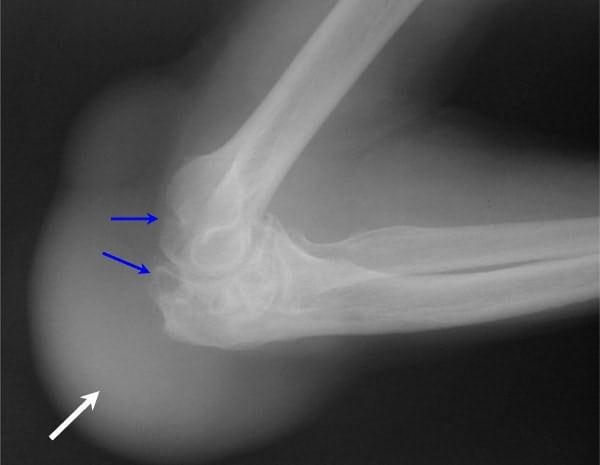

Какие обследования может назначить врач

Для уточнения диагноза специалисту потребуются результаты дополнительных методов исследования. Обнаружить воспаление в разных структурах локтевого сустава можно с помощью рентгенографии и УЗИ. Рентгеновские снимки делают в двух проекциях.